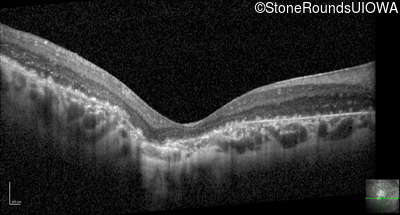

Optical Coherence Tomography - Right - 20/200 +1

Exemplar / OCT Stack